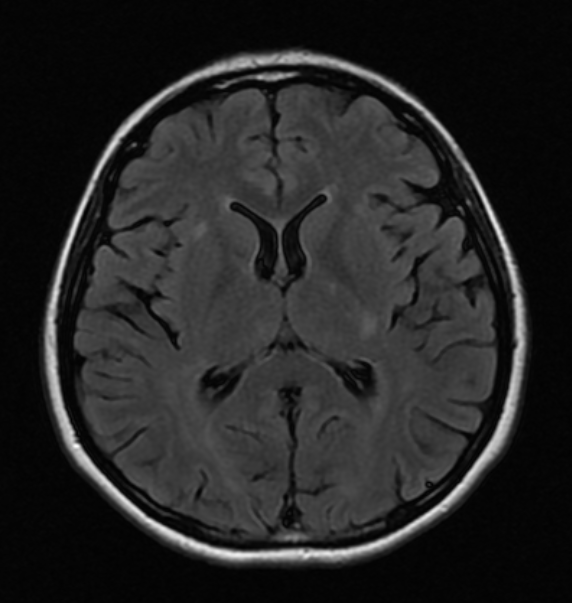

Objetivo: Relatar o caso de recidiva de herpes-zoster (HZ) em paciente com esclerose múltipla (EM) em uso de tratamento imunomodulador (natalizumabe) com evolução favorável. Descrição de caso: Mulher de 39 anos com diagnóstico de EM há 1 ano e 6 meses, previamente tratada com interferon 1a, começou tratamento com natalizumabe, desenvolvendo HZ após três meses de tratamento. HZ foi tratado com aciclovir, por sete dias, via oral. Seguimento ambulatorial após três meses de tratamento mostrou resolução completa das lesões, sem desencadeamento de neuralgia pós-herpética. Conclusões: As novas terapias para a EM podem estar relacionadas a diferentes tipos de efeitos adversos. Nem todos os casos de HZ, associados com novas terapias para EM, evoluem de forma desfavorável. Estudos são necessários para reconhecer os fatores de riscos para as formas graves de HZ em tais pacientes.